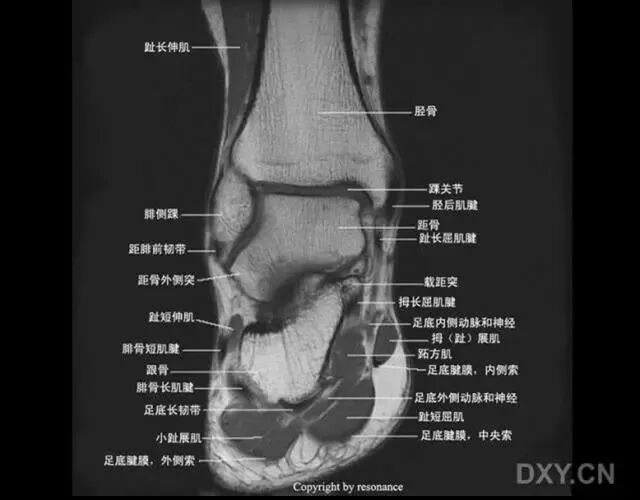

距骨在踝穴内有无倾斜,会通过影响关节面接触面积而影响关节所受应力的大小。有轻度倾斜,关节面所受到的应力会因为承重面积变小而明显增加。

旋后位扭伤最为常见;

距骨体前宽后窄,当踝关节背屈时,其宽部进入踝穴,能防止踝关节向后脱位;当跖屈时,其窄部进入踝穴,则关节不稳,易向侧方活动。